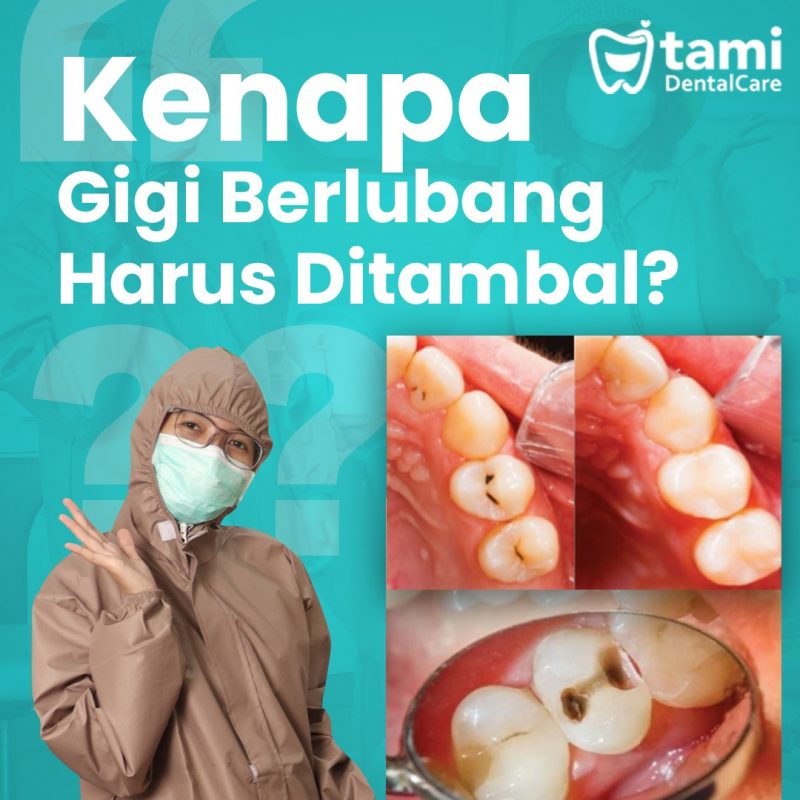

Prosedur Tambal Gigi Berlubang Yang Perlu Kamu Ketahui – Teman Dental

source: www.temandental.co.id

Prosedur Tambal Gigi Berlubang Yang Perlu Kamu Ketahui – Teman Dental …

Gigi Berlubang Parah, Dicabut Atau Ditambal? Ini Kata Ahli – ERA.ID

source: era.id

Gigi Berlubang Parah, Dicabut atau Ditambal? Ini Kata Ahli – ERA.ID

Contoh Gigi Yang Masih Bisa Ditambal – 54+ Koleksi Gambar

source: www.kibrispdr.org

Contoh Gigi Yang Masih Bisa Ditambal – 54+ Koleksi Gambar

Kenapa Gigi Yang Sudah Ditambal Permanen Masih Terasa Sakit

source: www.perumperindo.co.id

Kenapa Gigi Yang Sudah Ditambal Permanen Masih Terasa Sakit …